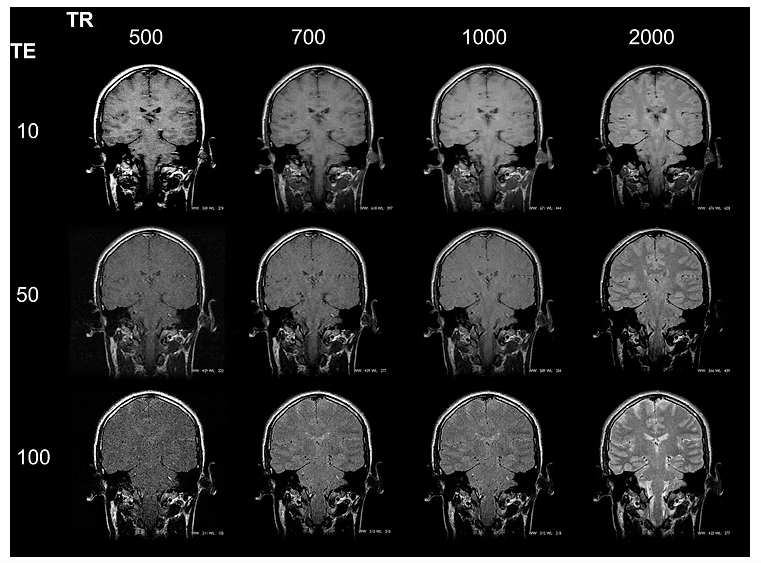

🔧 Parâmetros de Aquisição

Para obter sequências T2 ou T2*, alguns parâmetros precisam ser ajustados:

| Parâmetro | T2 (FSE/SE) | T2* (GRE/SWI) |

|---|---|---|

| TR | ≥ 2000 ms | 300–800 ms |

| TE | ≥ 80 ms | 15–40 ms |

| Flip Angle | 90° | 10° a 30° |

| Tipo de sequência | Spin Echo / FSE | Gradient Echo / SWI |